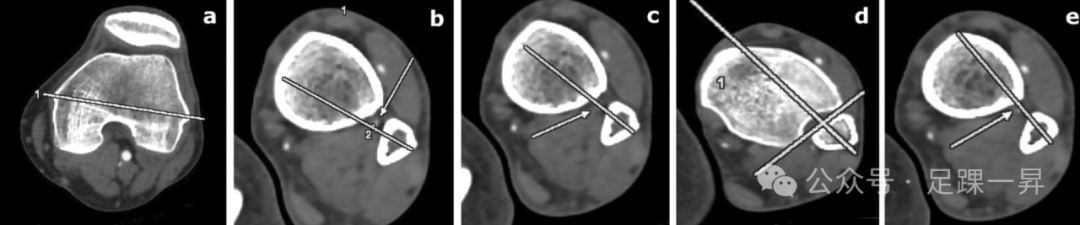

▲图示下胫腓联合置钉所需的轴线及其与腓动脉的关系。箭头显示腓动脉。在b、c和e处,三种不同直径的螺钉选项有可能损伤腓动脉。a 经上髁股骨轴。b 20°下胫腓联合螺钉角度的轴线。该水平距离踝关节线近端2.5cm。轴线到腓动脉的最近距离为0.9mm。c 30°联合螺钉角的轴线。该水平距离踝关节线近端2.5cm。该图指出了模拟的下胫腓联合螺钉轴和腓动脉的重叠。d垂直于腓切迹的单个下胫腓联合螺钉角度。该水平距离踝关节线近端0.5cm。e 在距踝关节3cm以上,与骨间韧带平行的单个下胫腓联合螺钉角度。请注意腓动脉与下胫腓联合螺钉轴的接近程度。